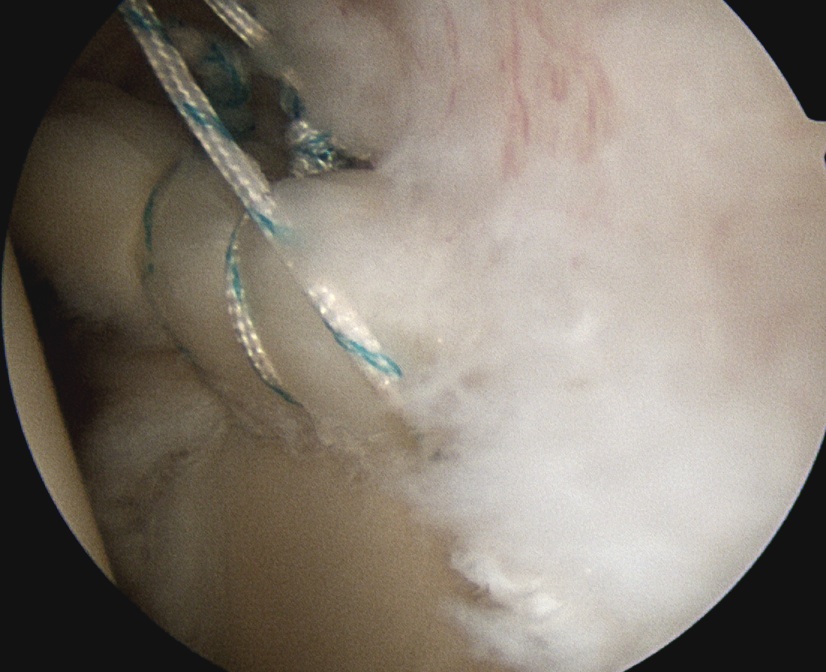

Posterior 2 anchors

- pass suture passer under biceps